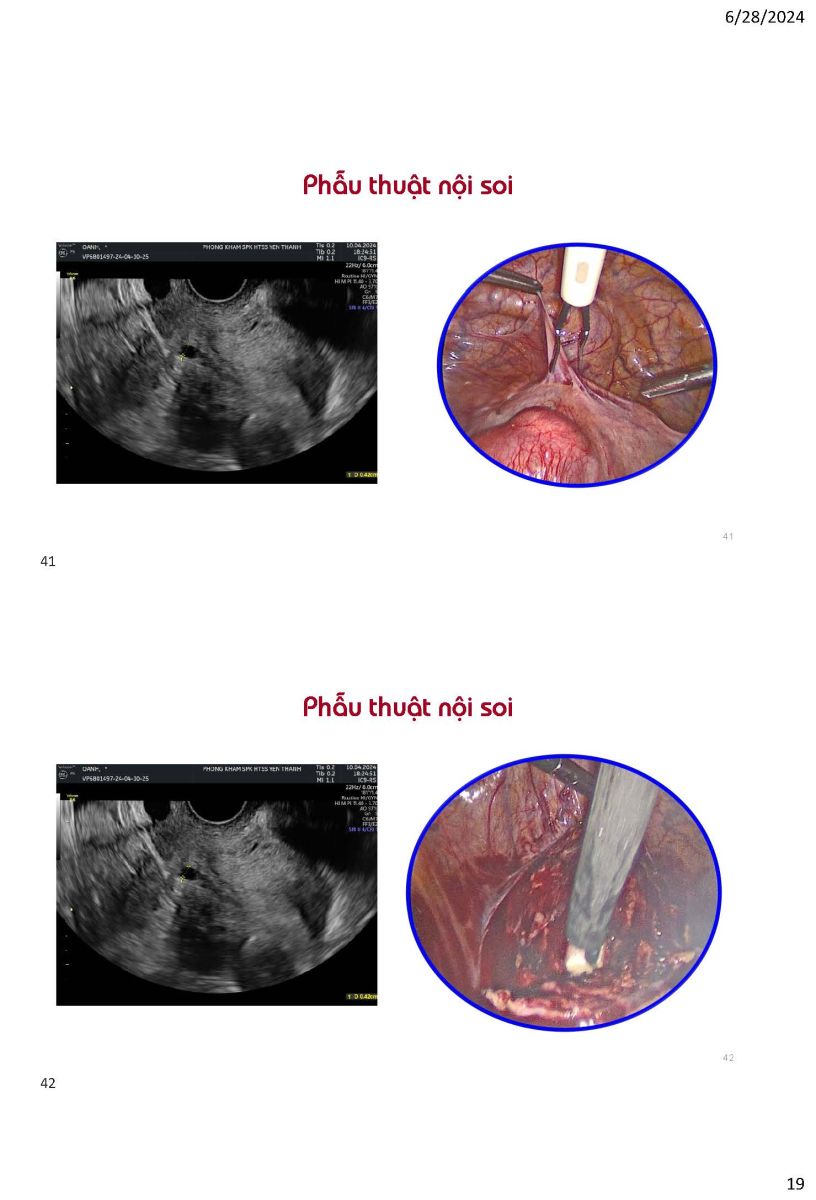

Ứng dụng siêu âm trong quyết định phương pháp can thiệp khuyết sẹo mổ lấy thai

Từ khóa: Ứng dụng siêu âm trong quyết định phương pháp can thiệp khuyết sẹo mổ lấy thai